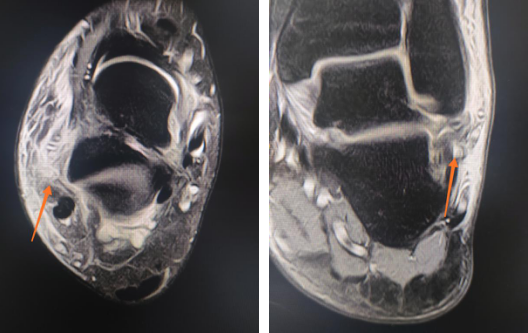

男孩跟骨骨折,距下关节镜微创撬拨复位

患者为12岁男孩,从高处坠落,导致跟骨粉碎性骨折。

2020年8月,必威官方首页官网betway足踝科曹广超主任手术团队为小患者进行了关节镜下撬拨复位内固定术,这一微创手术切口不到1cm,以4枚空心螺钉固定骨折,手术效果很好,男孩不到一周便出院回家。

距下关节镜下微创内固定治疗相比传统的手术方法,其优点为:高精度的微创性质,利用关节镜对距下关节空间的直接可视化,降低组织的创伤,更好地复位关节面;在固定骨折的同时可以修复软组织和软骨的损伤,进行多方面干预;减少传统切开复位可能导致的皮肤坏死;距下关节镜下治疗跟骨骨折,术中在监视下行骨折的解剖复位,尽可能地恢复距下关节面,最大限度提高了治疗效果。

男生蹦下楼梯右踝骨折,踝关节镜下微切口复位骨折修复韧带

患者15岁,蹦下楼梯时扭伤右脚踝,导致右外踝骨折,右外踝关节侧副韧带断裂。

2020年9月,sararz足踝科二病区徐明亮主任团队采用踝关节镜为这名右踝骨折的初中男生进行了关节镜下骨折复位内固定、韧带修复踝关节稳定术,手术很顺利,术后第四天,男生就出院回家休养。

踝关节镜技术相对开放手术的特点很明显:1、小切口,瘢痕小,周围组织损伤轻;2、镜下观察的踝关节范围大;3、恢复时间短,早期行康复锻炼。

韧带受伤

右外踝骨折(左),术中(右)